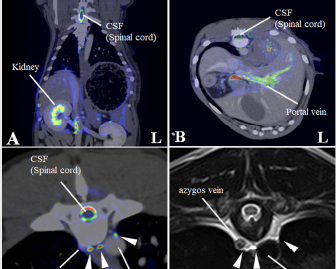

Fig. 1. Maximum intensity projection imaging of magnetic resonance thoracic ductography (MRTD). Cerebrospinal fluid, pleura, and kidney (renal pelvis) are shown (A, C). Unnecessary fluids were removed to construct the 3D image of MRTD (B, D). (A) Unprocessed MRTD image of the dorsal plane. (B) Processed MRTD image of the dorsal plane. (C) unprocessed MRTD image of the sagittal plane. (D) Processed MRTD image of the sagittal plane.

The raw MRI and CT data were transferred to a workstation (VAZE: PetCommunications, Chuo, Osaka, Japan) to construct the 3D images. In the MRTD images, the cerebrospinal fluid, pleura, kidney (renal pelvis) (Fig. 1A and C), part of the vessels (caudal vena cava, hepatic vein, and portal vein), and gastric juice were shown. Unnecessary fluids were removed in the maximum intensity projection (MIP) imaging of MRTD (Fig. 1B and D). Furthermore, 3D image of the thoracic duct was reconstructed from MRTD images, and 3D images of bone, heart, vessel, and esophagus were reconstructed from CT images. Those images were superposed using the “fusion” function on the workstation. The cerebrospinal fluid, kidney (renal pelvis), aorta, and liver vein (hepatic vein and portal vein) were used as indices of the superpose methods (Fig. 2A–C). The number of thoracic ducts at each vertebra between C5 andL2 were recorded in transverse MRTD (Fig. 2C) and T2WI (Fig. 2D). Location in relation to aorta and the location of the branches of thoracic duct were noted where possible. The comparison of the number of thoracic ducts at each vertebra between transverse T2WI and MRTD was performed using Student’s t-test. Statistical significance was set at p < 0.05.

Fig. 2. Merged images from magnetic resonance thoracic ductography (MRTD) and contrast enhancement CT. The spinal cord, kidney, hepatic vein, aorta and portal vein were used as indices of the superpose method (A, B, C). The number of thoracic ducts at each vertebra between C5-L2 were recorded in transverse MRTD (C) and transverse T2-weighted image (D). (A) Fused image of the dorsal plane. (B) Fused image of the transverse plane. (C) Fused image of the transverse plane at the level of T7. Contrast enhancement CT image (monochrome); MRTD (rainbow). (D) T2-weighted image of the transverse plane at the level of T7. CSF: cerebrospinal fluid, white arrows (thoracic duct).